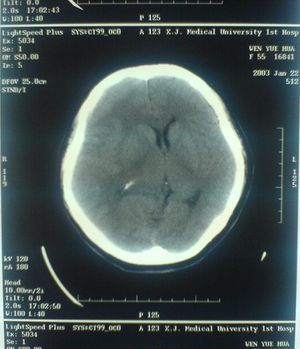

الأشعة المقطعية أو التصوير المَقْطَعي الحاسوبي Computed tomography نظام تصوير بالأشعة السينية، يُسْتخدم لتصوير مختلف أجزاء الجسم مثل الرأس والقلب والبطن. ويستعين الأطباء بالتصوير المقطعي الحاسوبي على تشخيص الأمراض وعلاجها. وتسمى هذه التقنية أيضًا التصوير المقطعي المحوسب أو التصوير المقطعي المحوري المحوسب.

وللحصول على صورة أشعة مقطعية، يرقد المريض على طاولة تمر من خلال آلة فحص دائرية، تسمى المِسْند. وتوضع الطاولة بحيث يكون العضو المراد فحصه واقعًا عند منتصف المسند. وعن طريق أنبوب على المسند، تخرج أشعة سينية مخترقةً جسد المريض، ثم تدخل إلى مكشافات خاصة تقوم بتحليل الصورة التي ظهرت. ويدور المسند حول المريض للحصول على كثير من الصور من زوايا مختلفة. وبعد ذلك، يعالج الحاسوب المعلومات الآتية من المكشافات، لينتج صورة مقطعية مستعرضة على شاشة فيديو. وعن طريق تحريك الطاولة داخل المسْند، يمكن للأطباء الحصول على العديد من الفحوص للعضو نفسه، أو للجسد كله.

ويستعمل الأطباء فحوص التصوير المقطعي الحاسوبي لتشخيص كثير من الحالات مثل الأورام والإصابات وتجلطات الدم وكسور العظام. ويساعد التصوير المقطعي الحاسوبي أيضًا في معالجة بعض الأمراض، التي قد تتطلب جراحة بطريقة أخرى. فمثلا،ً يمكن للأطباء استعمال التصوير المقطعي الحاسوبي لإرشادهم إلى إدخال القثطار (أنبوب رفيع) إلى خُرّآج في الجسم لسحب الصديد من المنطقة الملوثّة.